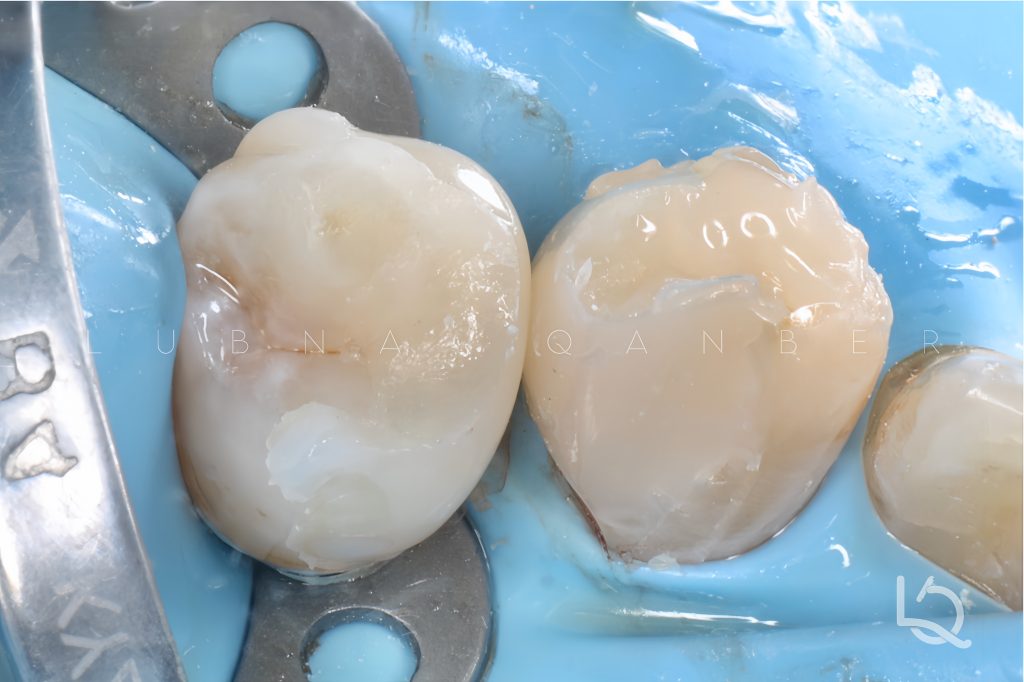

For this procedure, Bioclear matrices were used, as they provide excellent emergence profile reproduction and enable broad contact areas both buccolingually and occluso-apically.

The canine was restored first, taking advantage of the self-sealing capacity of the Bioclear matrix.

A deep margin elevation was performed on the premolar with delayed wedging to prevent matrix collapse. An Elliot separator was used to achieve proper tooth separation. Then, composite buttons were placed externally to further stabilize the matrix during injection of heated composite paste.